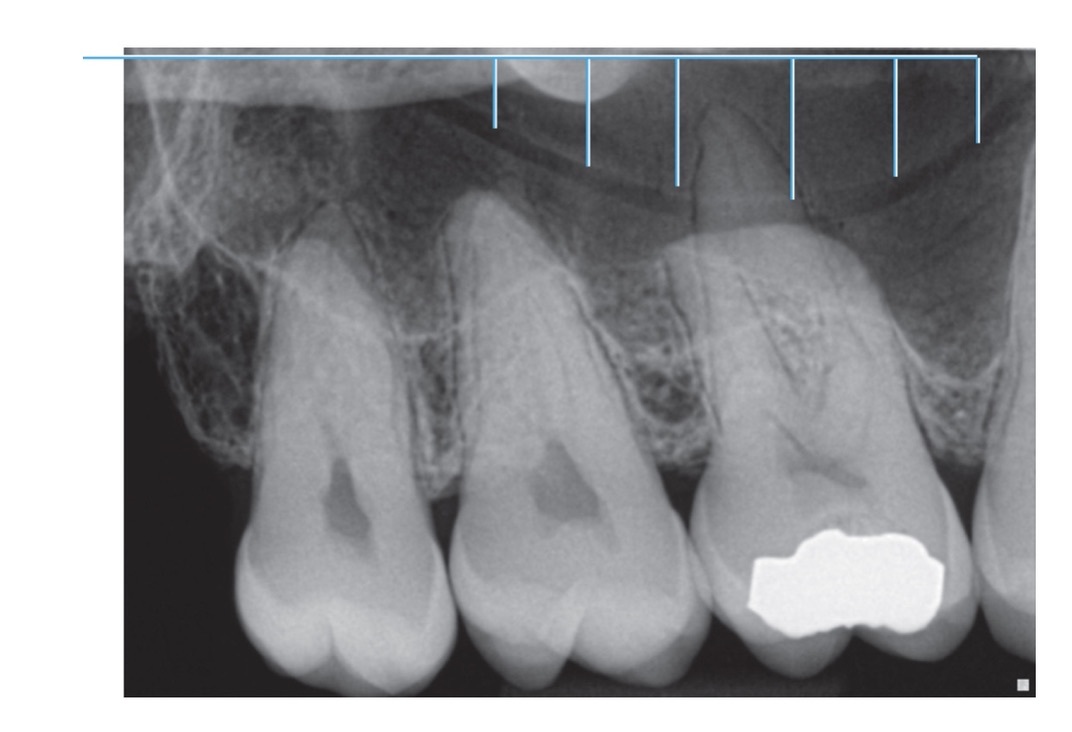

1.

Full metal crowns form bridge abutments

Identify the age of this patient

Age 12

Name the classification of dental caries illustrated by 3

C-3 Advanced Caries

Advanced: Lesion that extends to or through the DEJ but does not extend more than half the distance to the pulp

Identify the following:

(tube-like passageways through bone supplying blood vessels and nerves to maxillary teeth and bone, appear as narrow bands)

Nutrient Canals in Max Sinus